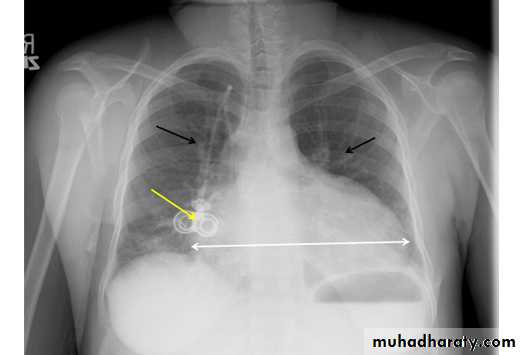

48.opasified hemi thorax Total collapse

Homogenus opacity of the right hemithorax with shifting of the trachea to the same side48.opasified hemi thorax Total consolidation

Homogenus opacity of the left hemithorax with central trachea

Total collapse

Homogenus opacity of the left hemithorax with shifting of the trachea to the same sidePleural effusion